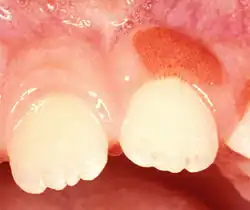

Plasma cell gingivitis in 7-year-old child. Histologically verified.

Plasma cell gingivitis in a 10-year-old child. Histologically verified.

Plasma cell gingivitis appears as mild gingival enlargement and may extend from the free marginal gingiva on to the attached gingiva.[6] Sometimes it is blended with a marginal, plaque induced gingivitis, or it does not involve the free marginal gingiva. It may also be found as a solitude red area within the attached gingiva (pictures). In some cases the healing of a plaque-induced gingivitis or a periodontitis resolves a plasma cell gingivitis situated a few mm from the earlier plaque-infected marginal gingiva. In case of one or few solitary areas of plasma cell gingivitis, no symptoms are reported from the patient. Most often solitary entities are therefore found by the dentist.[2]

The gums are red, friable, or sometimes granular, and sometimes bleed easily if traumatised.[6] The normal stippling is lost.[7] There is not usually any loss of periodontal attachment.[6] In a few cases a sore mouth can develop, and if so pain is sometimes made worse by toothpastes, or hot or spicy food.[7] The lesions can extend to involve the palate.[7]